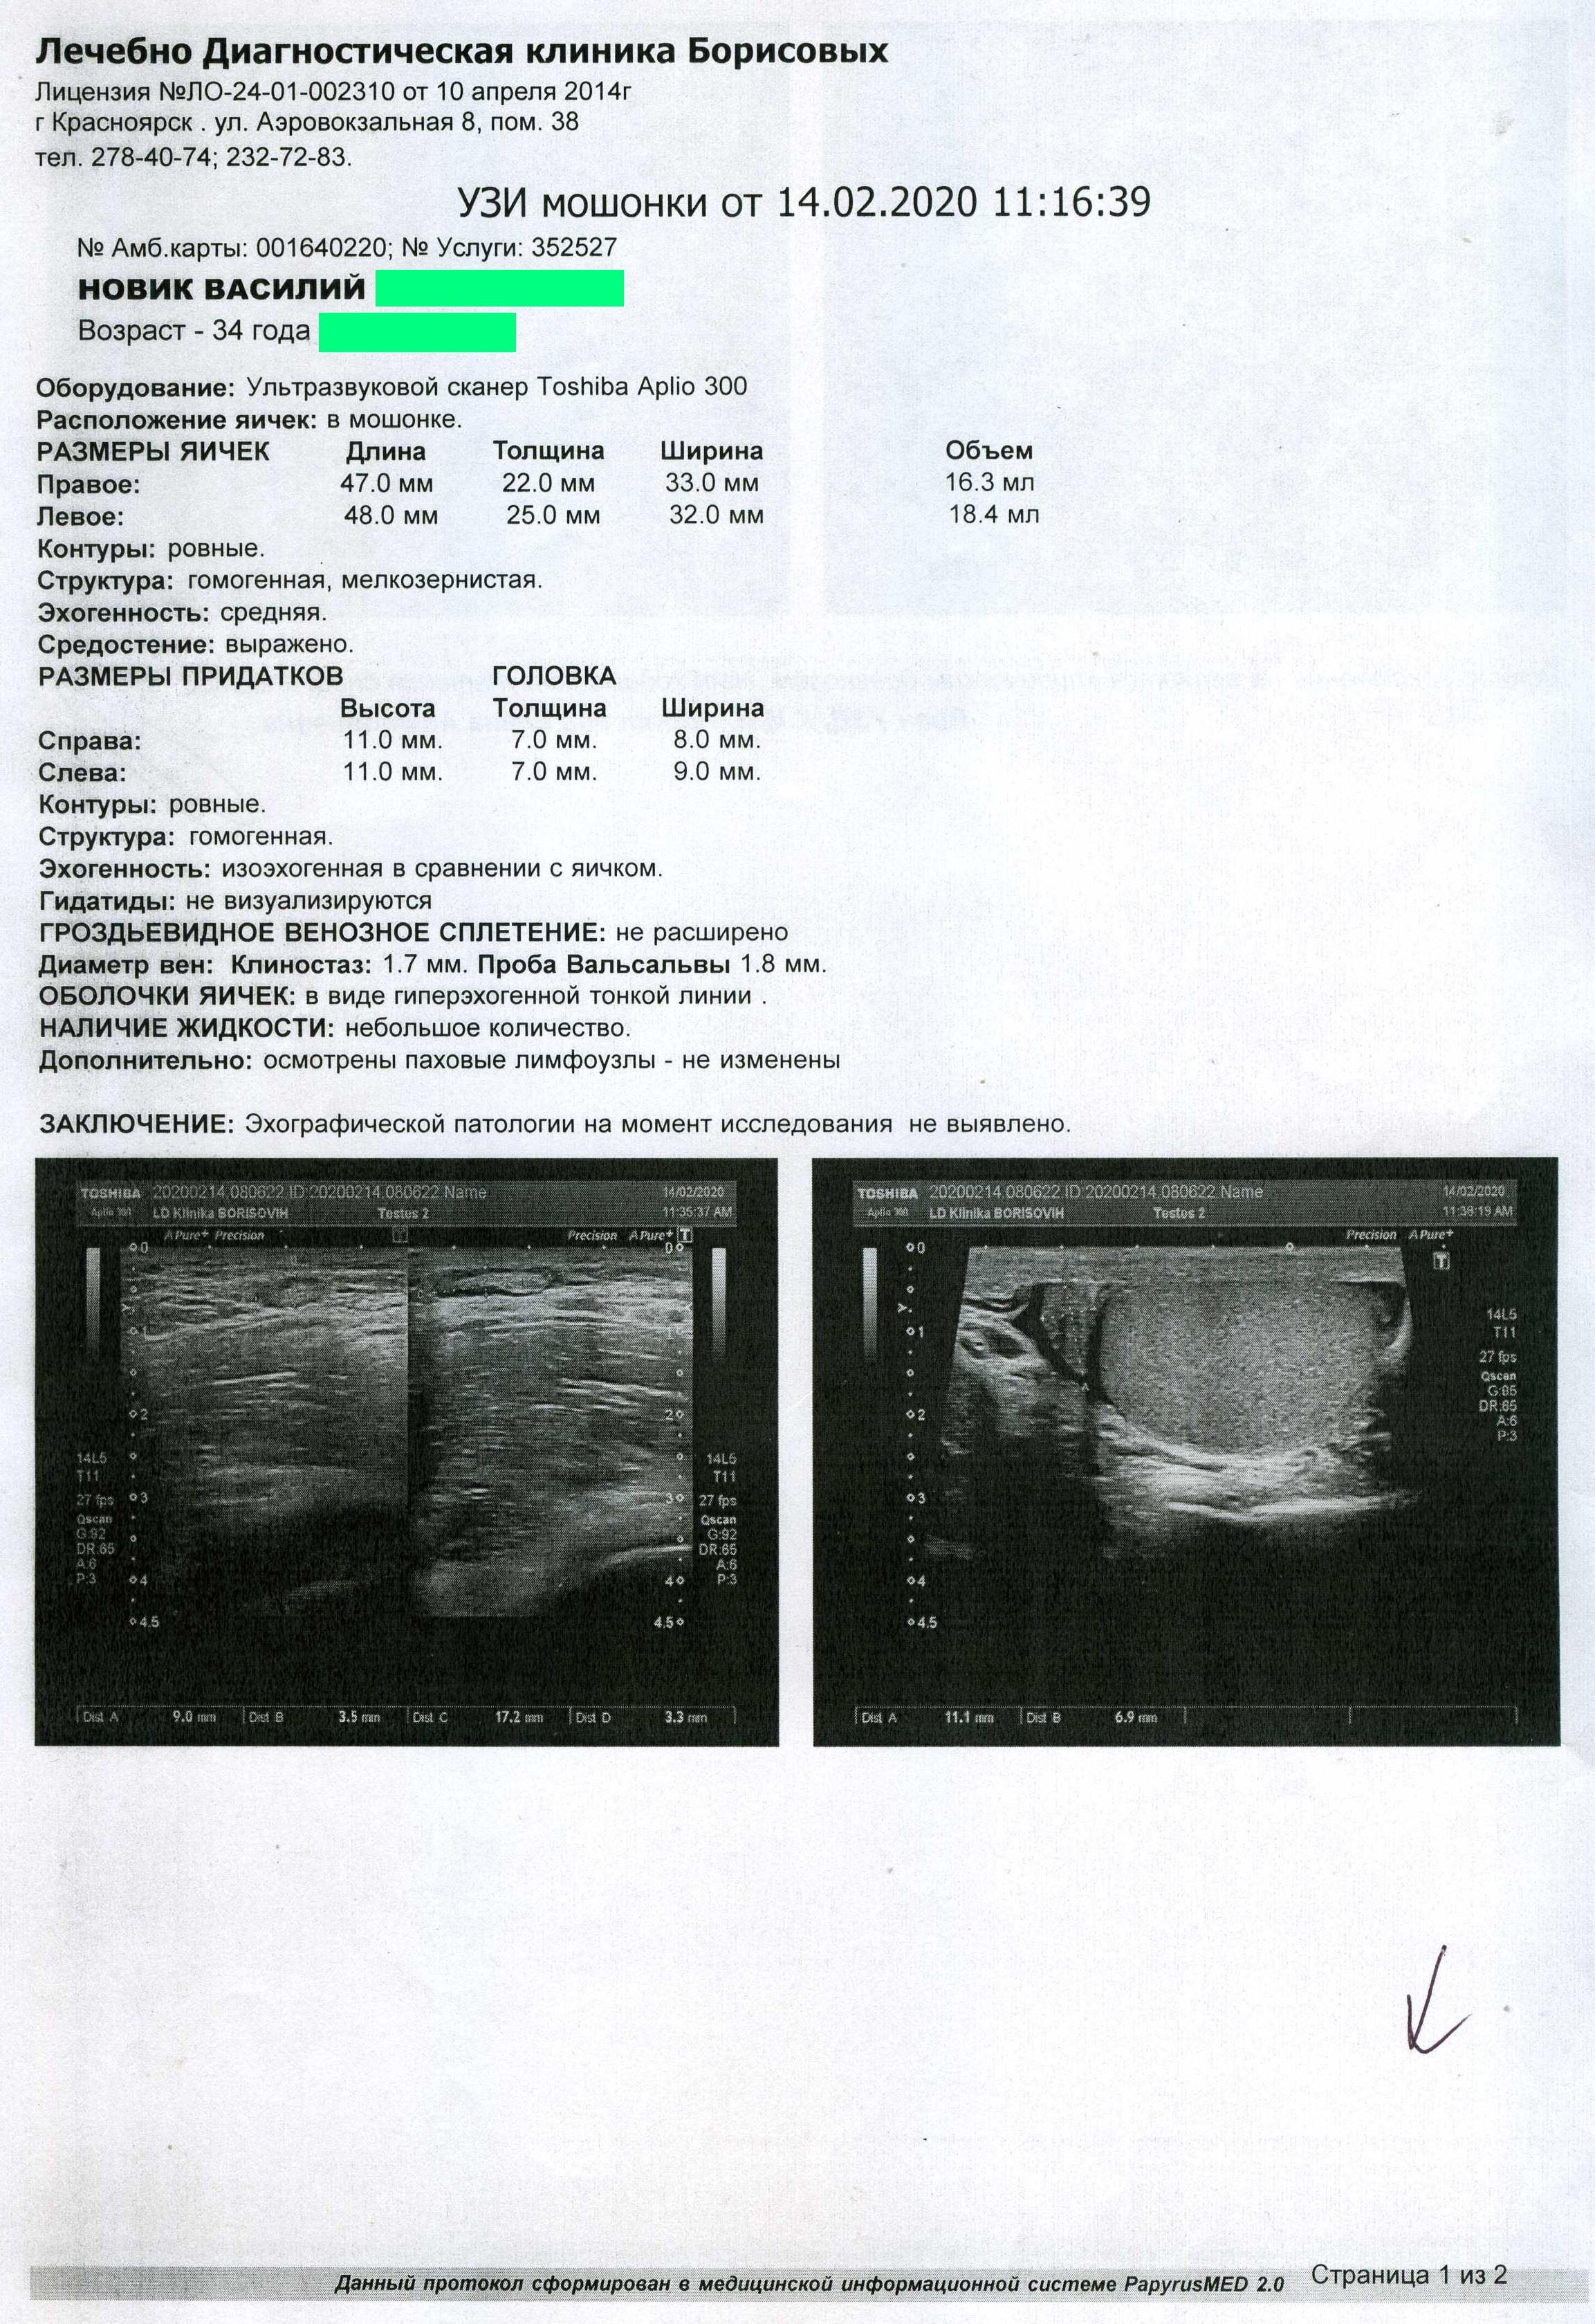

НА ДНЯХ СДЕЛАЛ УЗИ МОШОНКИ И ПРОСТАТЫ, ТАК ВОТ ПО ЯИЧКАМ ТИПА ВСЕ НОРМ А ВОТ В ПРОСТАТЕ ФИБРОЗНЫЕ ИЗМЕНЕНИЯ ПОХОДУ МОЧЕИСПУСКАТЕЛЬНОГО КАНАЛА И В ПРАВОЙ ДОЛЕ.

МОЖЕТ ЛИ ФИБРОЗ ДАВАТЬ БОЛИ В ЯИЧКА? И ЧТО ДНЛАТЬ С ТАКИМ ФИБРОЗОМ? ФОТО АНАЛИЗОВ ПРИЛАГАЮ. По крови повышены лимфоциты